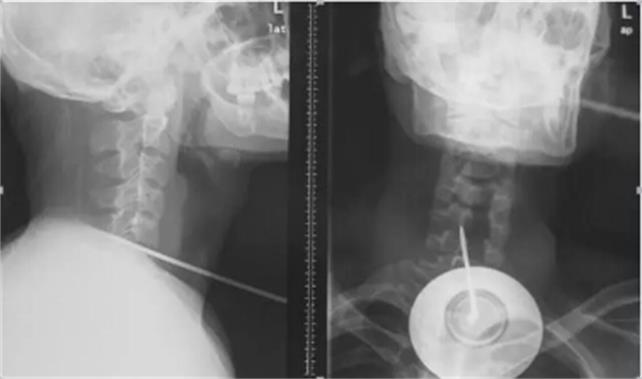

2月13日凌晨3時,上海長征醫(yī)院上演了一場真實(shí)版的“生死時速”。一根長約17厘米的鋼針從患者頸部正中穿入氣管、食管,通過椎體,貫穿脊髓,直達(dá)后路椎板穿出,生命危在旦夕。海軍軍醫(yī)大學(xué)長征醫(yī)院多科專家聯(lián)手合作,緊急手術(shù),展開了一場驚心動魄的生死大援救,成功拔出了奪命鋼針。術(shù)后第二天,患者癱瘓的右側(cè)上下肢功能明顯恢復(fù)。

2月12日午夜時分,長征醫(yī)院急診室接到120急救中心電話,有一名鋼針穿入頸椎,傷及氣管、食管,患者生命垂危。接到警情,急救科值班人員迅速開通搶救綠色通道,做好搶救措施。凌晨2時,救護(hù)車風(fēng)馳電掣停在急診室門口。23歲的小陳,只身一人在上海打工,工作時意外跌倒,頸部刺入一長約17厘米的鋼針。工友發(fā)現(xiàn)后將其送到上海一家大醫(yī)院,醫(yī)生認(rèn)為患者病情嚴(yán)重,建議立即轉(zhuǎn)診至全國脊柱外科技術(shù)實(shí)力強(qiáng)的醫(yī)院——海軍軍醫(yī)大學(xué)長征醫(yī)院救治。

然而,手術(shù)麻醉成了******道難題。由于鋼針將氣管、食管、脊髓固定在椎體上,無法進(jìn)行麻醉插管,耳鼻咽喉科徐亞平醫(yī)生另辟蹊徑,從鋼針下游,切開氣管實(shí)施插管,避免出血進(jìn)入氣管引起窒息。隨后,麻醉科鄭棟煜迅速完成傷者全身麻醉。首先脊柱二科史建剛教授采用頸部右側(cè)切口,游離皮下間隙,進(jìn)入椎間間隙,只見氣管、食管椎間盤被鋼針貫穿,醫(yī)生細(xì)心顯露頸5、6椎間盤前部,在確保周圍頸部大動脈不被鋼針損傷時,以***快的速度拔除鋼針。突然發(fā)生了驚險一幕,拔出鋼針后,大量的腦脊液和鮮血往外涌出,醫(yī)生迅速鉗夾控制出血,修補(bǔ)硬脊膜,并對損傷嚴(yán)重的頸部兩個骨贅進(jìn)行切除,徹底減輕脊髓壓迫。隨后胸心外科陸昕冶醫(yī)生仔細(xì)尋找食管、氣管壁破損缺口,進(jìn)行了縫合修補(bǔ),止住了食管、氣管漏。經(jīng)過3小時“戰(zhàn)斗”,小陳終于闖過了“鬼門關(guān)”。

據(jù)主刀醫(yī)生史建剛教授介紹,頸部解剖復(fù)雜,有頸部血管、氣管、神經(jīng)、食道、咽喉等重要結(jié)構(gòu),嚴(yán)重頸部創(chuàng)傷在受傷后往往因大出血及窒息而死亡,搶救成功率低。迅速診斷、及時手術(shù)、密切監(jiān)護(hù)、精準(zhǔn)救治是搶救成功的關(guān)鍵。此次成功救治患者,充分展示了長征醫(yī)院過硬的技術(shù)實(shí)力和強(qiáng)大的團(tuán)隊(duì)力量。